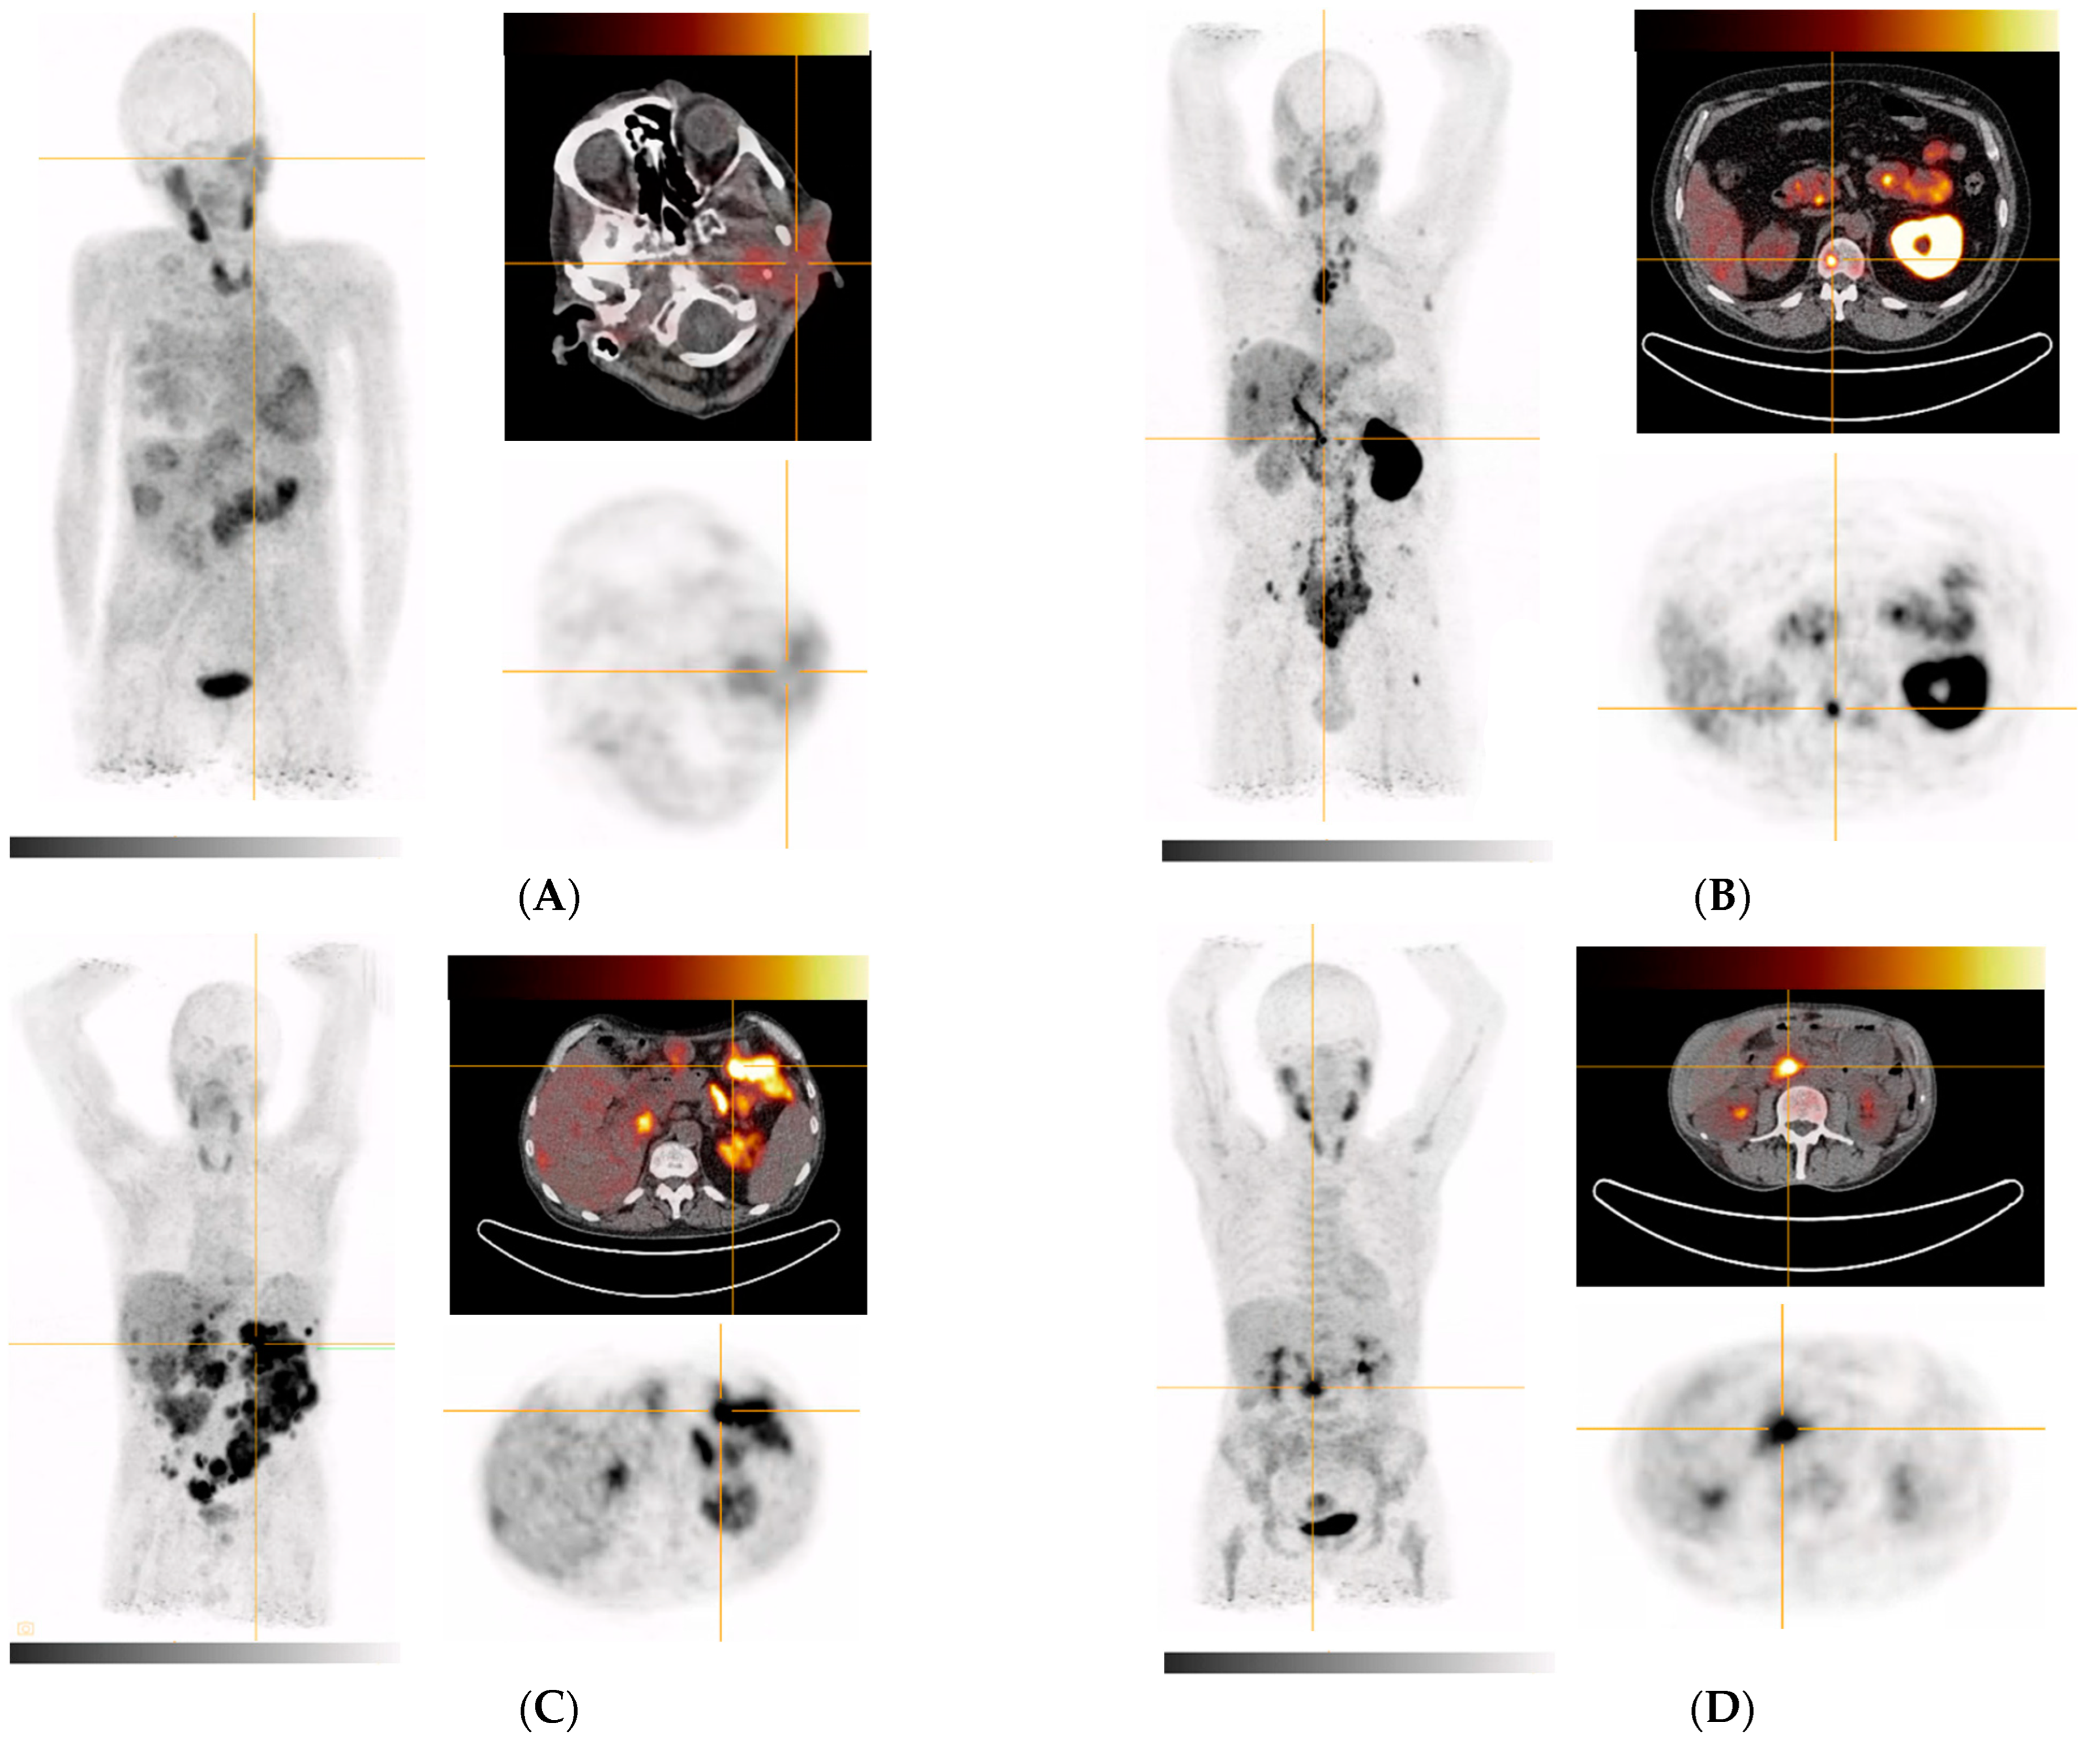

| 2 (Figure 4A) | Metastasized parotid gland tumor (adenoid-cystic subtype) | Subtotal parotidectomy (left), partial liver resection of segments II/III | Parotid gland, multiple masses in the right lung, accumulation in several liver segments |

| 3 (Figure 4B) | Metastasized prostate cancer (Gleason 4 + 3 = 7) | IMRT to prostate and seminal vesicles | Extensive bone and bone marrow involvement (including the extremities), large lymph node metastases in the retroperitoneum, mediastinum (bulky), and cervical region as well as in soft tissue. Additional findings: Severely impaired function of left kidney (slow wash out of activity with high parenchymal contrast and increased activity in the ureter and pelvis) |

| 4 (Figure 4C) | Metastasized liposarcoma | Tumor enucleation on the duodenum, pancreatic head resection, omentectomy, pancreaticogastrostomy | Extensive peritoneal tumor foci in all abdominal quadrants, caudal liver margin segment VI (or adjacent peritoneal foci) |

| 5 (Figure 4D) | Primary pancreatic head adenocarcinoma, moderately differentiated, ductal | ERCP with stenting | Inhomogeneous in the pancreas with emphasis in pancreatic head, peritoneal (extensively in the left mid to lower abdomen), anterior margin of liver (peritoneal or lymph nodes), mammaria interna lymph node, segment VI of the liver (most likely biliary excreted tracer), uterus (nonspecific/physiological), muscle attachments at the hip joints (nonspecific/inflammatory/bursitis) |